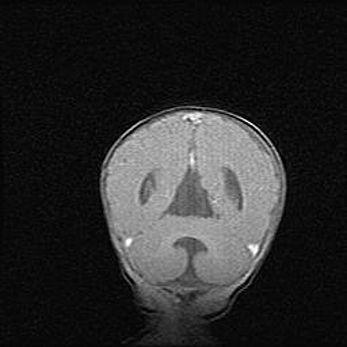

Наружная гидроцефалия с возможной атрофией височных областей.

Возраст: 28 дней

Вес: 3670 г

Пол: мужской

Окружность головы: 38 см

Срок гестации: 40 недель

Гидроцефалия головного мозга у новорожденных – это заболевание, которое характеризуется скоплением избыточного количества спинномозговой жидкости в желудочковой системе головного мозга в результате затруднения её перемещения от места выработки к месту поглощения в кровеносную систему или вследствие нарушения абсорбции. При открытой наружной форме гидроцефалии у новорожденных расширяются и переполняются субарахноидные пространства.

При нормотензивных  формах,  которые,  как  правило,  являются  следствием  перенесенных ишемических  повреждений  паренхимы  мозга,  возможно  сочетание микроцефалии  с нормотензивной гидроцефалией. В основе данных изменений лежит атрофия больших полушарий с преимущественной  локализацией  в  лобно-височных  областях.